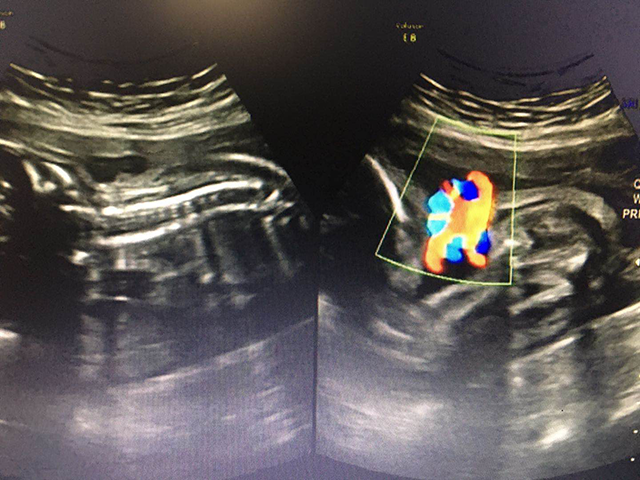

产前超声之胎儿脐带绕颈

来源:影像科 时间:2020-07-07 10:43:48 点击:产前超声之胎儿脐带绕颈

怀孕是一件幸福的事。随着肚子里的宝宝一天天的长大,孕妈妈们心里的担忧也逐渐增多。当孕妈妈们拿到超声报告,看到胎儿颈部见“U”型、“W”型压迹等等。这代表了什么呢?其实这些是脐带绕颈的间接表现,“U”代表宝宝可能有脐带绕颈1圈;“W”代表宝宝可能有脐带绕颈2圈。

胎儿脐带绕颈一周

胎儿脐带绕颈两周

当发现有脐带绕颈后可以结合胎心监护结果综合判断有无胎儿缺氧情况存在。超声上判断早期缺氧情况可以通过监测妊娠晚期脐动脉血流S/D值、大脑中动脉血流S/D值来判断。当然你也可以通过计数胎动次数来判断,方法如下:每天早中晚固定一个最方便的时间数3次胎动。在安静的状态下,注意力集中,双手置于腹部,用纽扣为标记,动一次放一枚纽扣在盒子中,如连续动一阵也算一次。